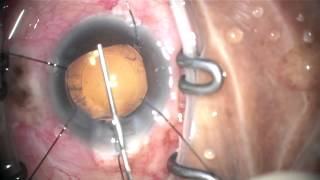

phacotrabectome, CTR in very advanced pseudoexfoliation glaucoma video

phacotrabectome, CTR in very advanced pseudoexfoliation glaucoma

phacotrabectome, CTR in very advanced pseudoexfoliation glaucoma beginner phaco-trabectome, failed trabeculectomy, very advanced pseudoexfoliation glaucoma

beginner phaco-trabectome, failed trabeculectomy, very advanced pseudoexfoliation glaucoma phacotrabectome, CTR, phacodonesis, small pupil: pseudoexfoliation glaucoma 20130218 #1

phacotrabectome, CTR in very advanced pseudoexfoliation glaucoma

phacotrabectome, CTR in very advanced pseudoexfoliation glaucoma beginner phaco-trabectome, failed trabeculectomy, very advanced pseudoexfoliation glaucoma

beginner phaco-trabectome, failed trabeculectomy, very advanced pseudoexfoliation glaucoma phacotrabectome, CTR, phacodonesis, small pupil: pseudoexfoliation glaucoma 20130218 #1